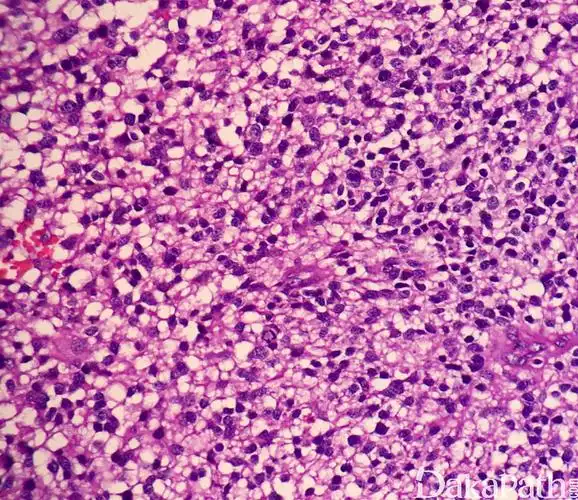

间变性少突胶质细胞瘤